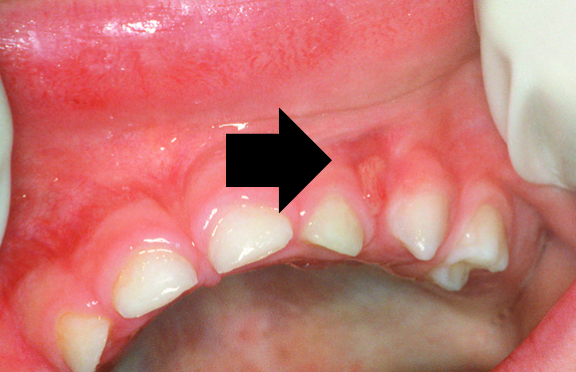

6.4 Gingival cysts

Gingival cysts are hard, raised nodules, and are classified as follows:

Epstein’s pearls — are small, white, pearl-like spots that appear in the middle of the hard palate (on the roof of the mouth). These bumps are harmless and tend to disappear within a few weeks.

Bohn’s nodules — are remnants of the dentinal lamina and occur on the labial (cheek side) of the maxillary alveolar ridges (gum ridge). These small, whitish bumps or cysts look like Epstein’s pearls, but can be differentiated by their site of presentation.

Prevalence

Gingival (keratin) cysts are relatively common in newborns. Epstein’s pearls occur in 60–85 per cent of newborns (Eichenfield & Larralde 2004). Bohn’s nodules occur in up to 85 per cent of newborns (Eichenfield & Larralde 2004).

Causes

Epithelial remnants trapped along lines of fusion of embryological processes.

Age

Usually occur in newborns. They are present in all children, but are normally shed in utero.

Duration

Nodules usually slough off in the first three months.

Treatment

No treatment is required other than the reassurance of parents